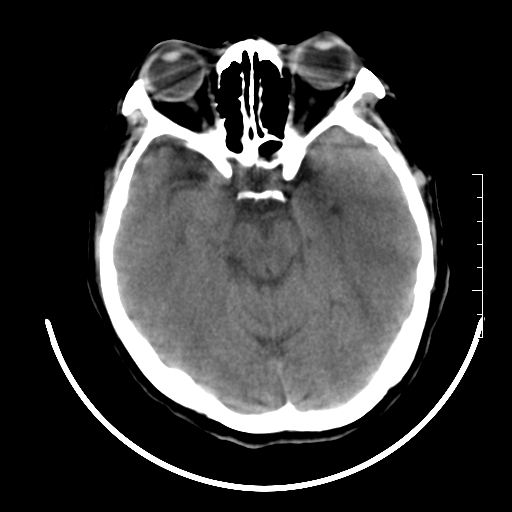

标题: CT27880:f、55y,头痛。 [打印本页]

标题: CT27880:f、55y,头痛。

考虑左侧顶部镰旁脑膜瘤;建议行ct增强扫描检查。

考虑左侧顶部镰旁脑膜瘤,建议行ct增强扫描检查。

考虑左侧顶部镰旁脑膜瘤;建议行ct增强扫描检查

大脑镰旁脑膜瘤可能,建议增强或mri

镰旁小脑膜瘤可能性大

左侧顶部镰旁脑膜瘤,增强